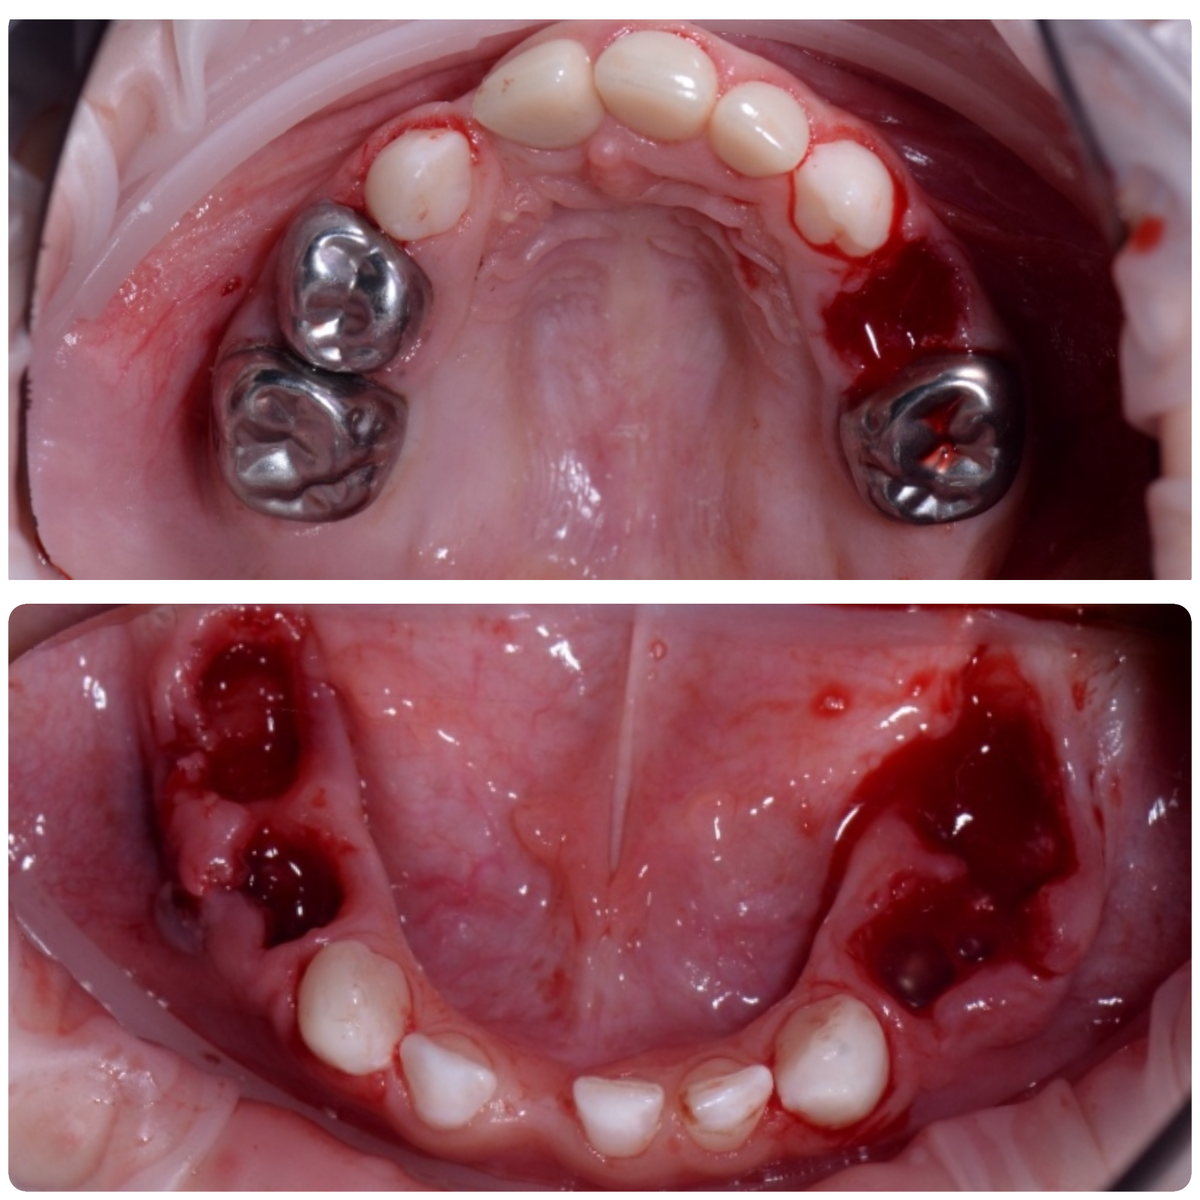

Чтобы такой звездец случился - нужно время и бездействие  Не удалять жевательные зубы было нельзя! Они сгнили и плавали в гное - это опасно для жизни и больно❌ В год с небольшим ребенку мы полечили часть Зубов - они и спаслись  Дальше родители решили полечить зубы в другой стране у врача -родственника, который совсем не детский  Да и лечить такие зубы не умел, про коронки не знал и т д, но полез  Потеряли время, не пришли за два года ни разу на осмотр  Да и сейчас, после второго наркоза опять пропали 🤷🏼‍♀️ В общем, мальчишку жаль.  Жевать ему пару лет точно нечем. Да и потом проблем будет немало, если решать их таким способом раз в несколько лет  Я не осуждаю, но очень злюсь. Потому что болит у детей , а не родителей. Удалять зубы , которые при своевременном лечении можно было спасти - это сомнительное удовольствие

Чтобы такой звездец случился - нужно время и бездействие

Не удалять жевательные зубы было нельзя! Они сгнили и плавали в гное - это опасно для жизни и больно❌

В год с небольшим ребенку мы полечили часть Зубов - они и спаслись

Жевать ему пару лет точно нечем. Да и потом проблем будет немало, если решать их таким способом раз в несколько лет